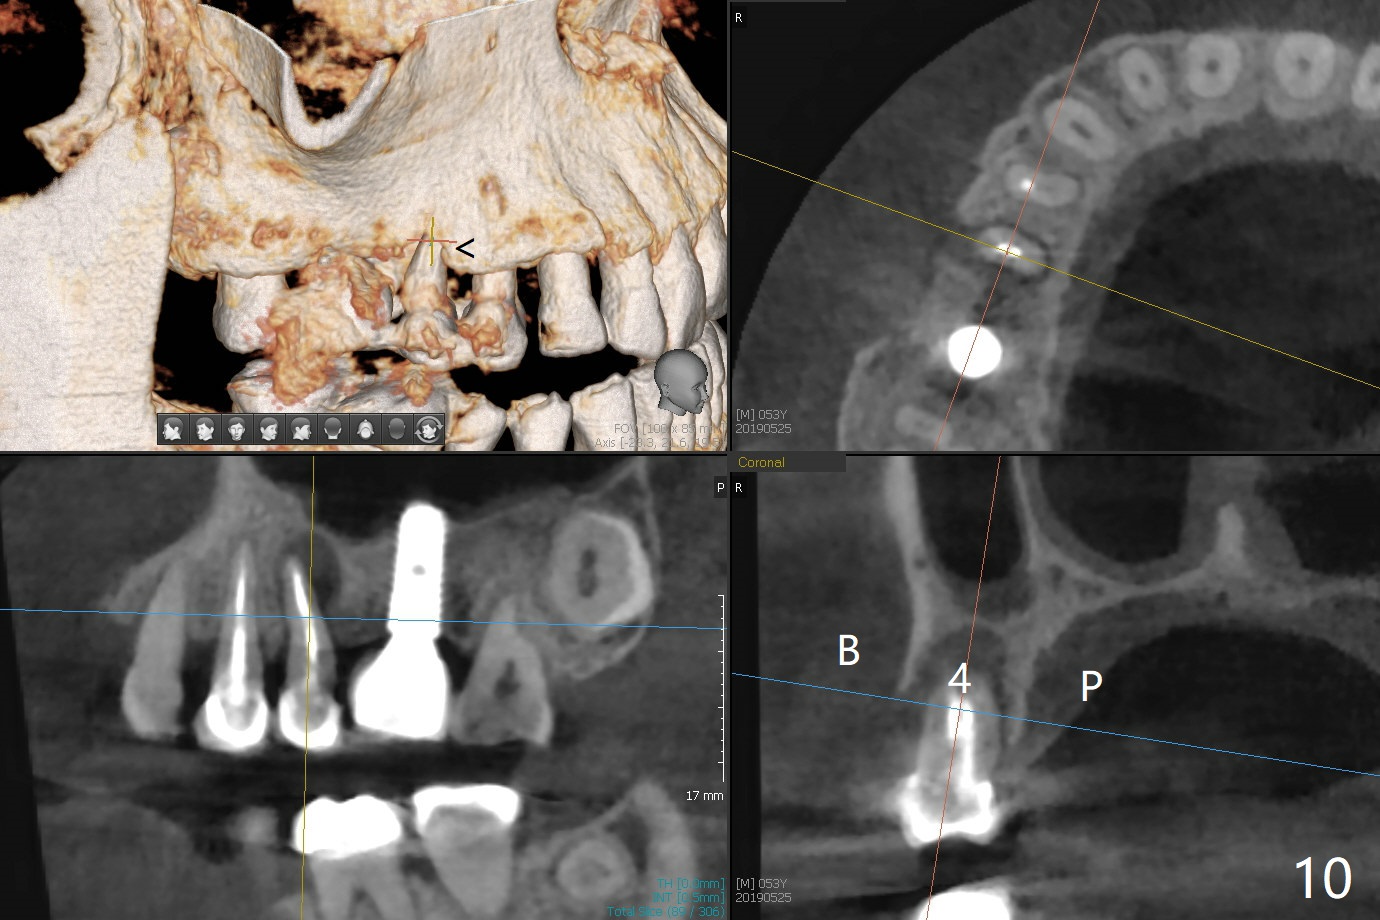

Crown/Implant Ratio

A 53-year-old man has signs of bruxism (Fig.1 diastema *) and root fracture or RCT failure at #4 (Fig.4 (large PARL *)). The RCT failure is related to overload of the affected tooth, which is in turn partially due to infraocclusion of the neighboring implant crown (Fig.1 arrows (implant positioning not ideal)) and partially to due to partial edentulism (Fig.2 missing teeth #14 and 18). For long term, limited ortho will be performed to upright and distalize the tooth #15 (Fig.3 arrow), followed by implants at #14 and 18. For now, the tooth #4 will be extracted (Fig.5), followed by osteotomy in the distal slope of the socket with guide (Fig.6 to get good trajectory). To place a bone-level implant (Fig.7 green), an abutment (blue) with long cuff (pink) is to be used. With poor implant/crown (white) ratio, stress occurs at the junction of the implant/abutment (red arrow), resulting in easy abutment screw loosening. In contrast, stress may be applied to directly to a tissue-level implant (Fig.8 arrow) with less likelihood of abutment screw loosening. The implant/crown ratio improves by approximately 5.5 mm. The roots of the teeth #15 and 16 are so close to each other that interference may occur when the tooth #15 is being uprighted (Fig.9). The empty socket of the tooth #4 is wide buccopalatal (Fig.10); the buccal plate is resorbed coronally (Fig.10 <) so that a 4.5 or 5 mm diameter implant should be placed palatal (Fig.11). Use sticky bone to repair the buccal plate defect and PRF membrane or plug for sinus lift. Following #15 uprighting and distalization, a 5x10 mm implant will be placed at #14; the ridge is triangular (Fig.12 <) so that bone trimmer is needed. A 10 mm long implant will be placed at #18 (Fig.14) to avoid perforating to the submandibular fossa (Fig.13 *).